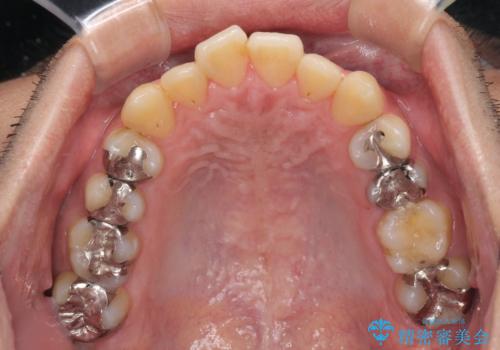

前歯のクロスバイトをインビザラインで矯正治療

- 前歯のデコボコとクロスバイトを気にして来院された患者様です。

前歯を早く整えたいとの希望があったので、ワイヤー矯正にて短期間でクロスバイトを解消し、その後インビザラインにて整えることとしました。